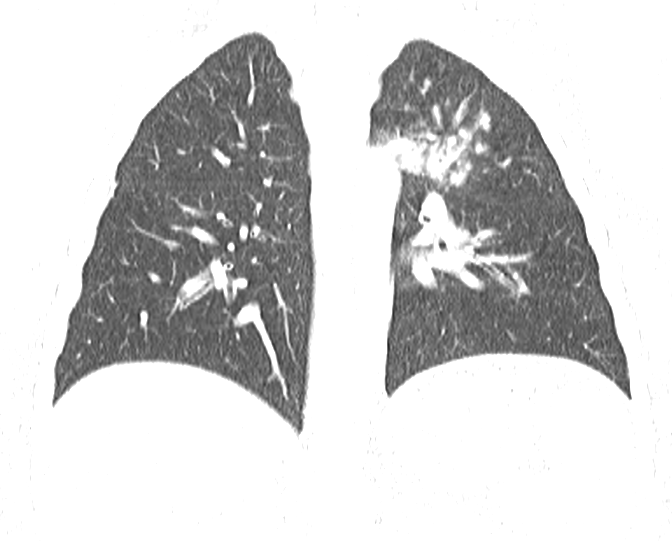

11살 소년

왼쪽부터 오른쪽 상엽으로 퍼진 흉부 X선, 흉부 CT 단면, 종단면